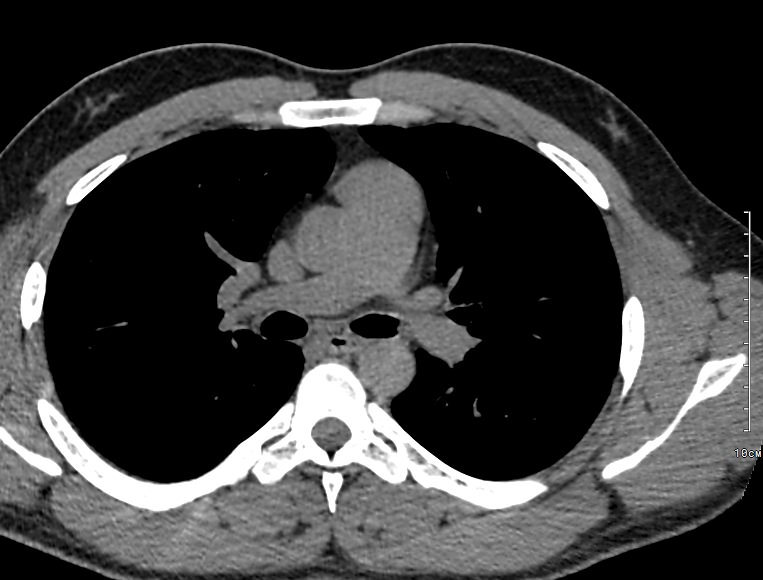

Одним из наиболее информативных методов исследования органов средостения является компьютерная томография. В основе метода лежит использование проникающего действия ионизирующего излучения для получения подробных снимков строения внутренних органов.

Инновационные технологии, которыми оснащены компьютерные томографы, послойно сканируют анатомическую область с шагом от 0,5 мм. В результате получаются снимки тонких срезов исследуемой зоны в мельчайших подробностях. С помощью цифровых приложений на основании полученных данных можно реконструировать трехмерные модели внутренних органов, что позволяет оценить структуру зоны исследования и близлежащих тканей.

Что показывает КТ органов средостения?

- наличие онкологии и метастазов;

- туберкулез и другие инфекции;

- патологии диафрагмы и бронхов;

- последствия травм;

- состояние лимфоузлов;

- индивидуальные анатомические особенности;

- патологии вилочковой железы;

- новообразования из нервной ткани;

- опухоли в жировой соединительной ткани;

- патологии мышечной ткани и сосудов;

- кисты;

- эмфизему средостения;

- абсцесс, эмпиему средостения;

- аневризму аорты

- воспалительные процессы;

- болезни сосудов и тромбоэмболию.